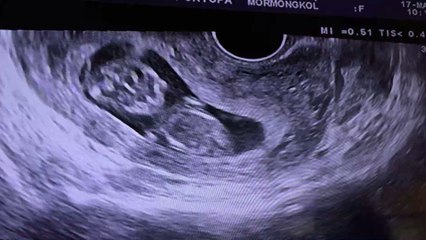

Deutschland: Krankes Neugeborenes so lange von Ärzten ignoriert, bis es zu spät ist